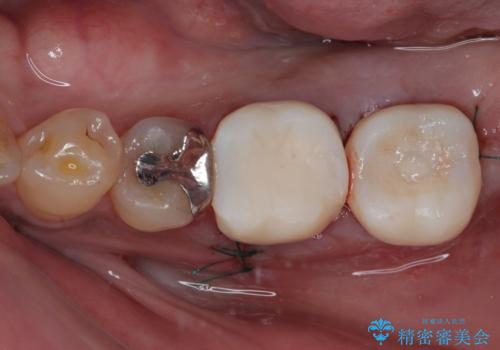

インプラント治療まで待機している間に、手前のむし歯処置されている歯が強い痛みに襲われ、確認したところ、既に神経組織が壊死している状態であったため、根管治療を行い、インプラント部と合わせて補綴治療を行いました。